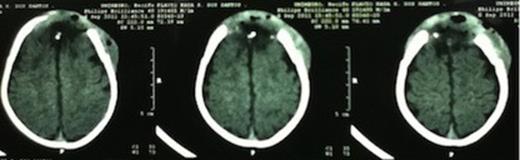

The patient was transferred to the intensive care unit and a CT scan of the brain was performed 48 hours after surgery (Fig. 4).